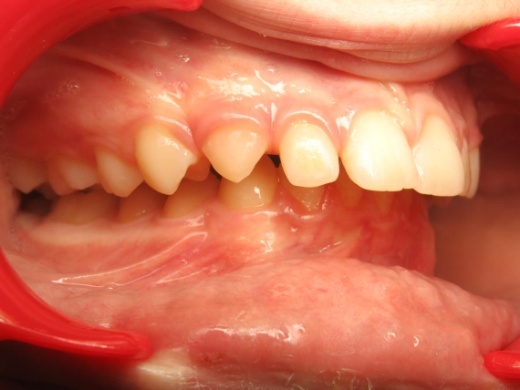

1 - Arcades dentaires avant-après

Les arcades dentaires montrent un décalage majeur de classe II, avec des incisives inférieures en position très reculée, venant directement au contact du palais. Cette configuration traduisait un déséquilibre squelettique important entre maxillaire et mandibule. Le traitement a consisté en une préparation orthodontique rigoureuse, suivie d’une chirurgie orthognathique permettant de repositionner les bases osseuses et de restaurer une occlusion fonctionnelle.